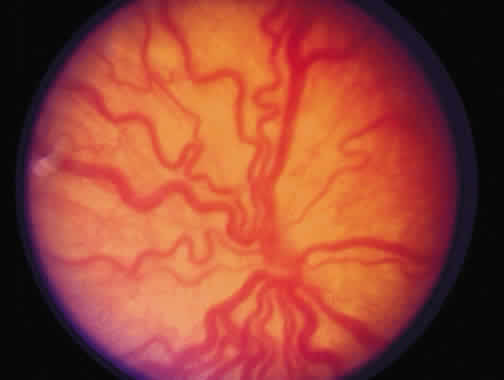

Laser is particularly useful in the management of zone I and posterior zone II disease. Most often, conjunctival incisions are necessary to get a cryotherapy probe posterior enough to treat zone I disease. This problem is obviated with laser delivery. Results of treatment of zone I disease in the Cryo-ROP Study are poor, whereas success rates of 80% to 90% have been reported in managing zone I disease with laser.71, 72, 73, 74, 75 Ridges in zone I or posterior zone II disease often are wider, with more defined vasculature than in zone II disease (Fig. 9). Zone I disease can be determined with a + 25 D lens. The disc is visualized at one rim of the lens, and avascular retina can be seen at the opposite rim when zone I disease is present (Fig. 10). A This occurs at a significant rate in the eyes of the smallest infants (500 g) with a gestation of 22 to 26 weeks. There may be an associated persistence of fetal vasculature (Fig. 11).